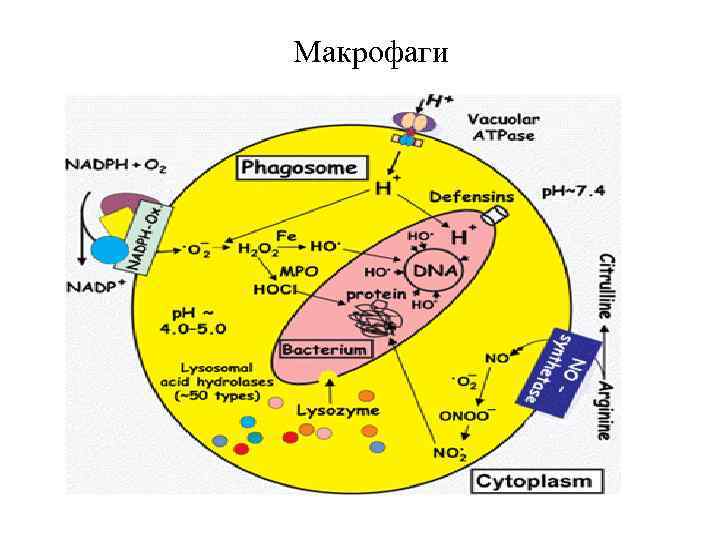

Уничтожение гельминтов лейкоцитами и макрофагами происходит при комбинированном действии низкого р. Н, кислородзависимых и кислороднезависимых повреждающих факторов, а также лизосомальных гидролаз.

Каким образом фагоцитирующие клетки уничтожают гельминтов? Кислороднезависимые механизмы (нейтрофилы)

Нейтрофилы секретируют большое количество соединений, способных разрушать клеточные мембраны паразитов без участия свободнорадикальных механизмов. Это: - дефенсины - эластаза - нейтральные протеиназы (катепсин G и подобные) Эти белки разрушают надмембранный матрикс атакуемой клетки и формируют крупные трансмембранные ионные каналы с неуправляемой проницаемостью.

Макрофаги

Каким образом фагоцитирующие клетки уничтожают гельминтов? Кислородзависимые механизмы